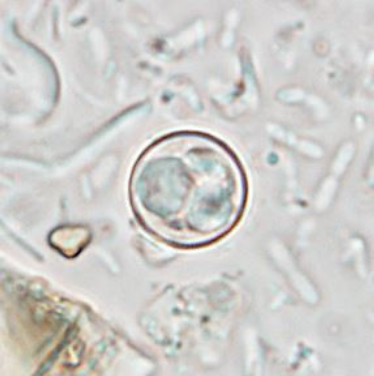

साइक्लोस्पोरा एक कोशिकीय (Single-celled) सूक्ष्म परजीवी है। यह इतना छोटा होता है कि इसे नग्न आंखों से नहीं देखा जा सकता। जब यह परजीवी शरीर में प्रवेश करता है, तो यह छोटी आंत (Small Intestine) को प्रभावित करता है, जिससे साइक्लोस्पोरियासिस (Cyclosporiasis) नामक बीमारी होती है।